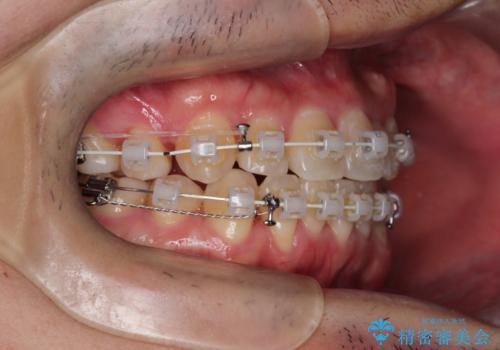

【重度叢生ワイヤー矯正】きれいな歯並びにしたい

- 審美装置

- きれいな歯並びにしたいとの希望を持って来院された患者様です。

上下左右小臼歯を抜歯する治療計画を立て審美装置にて治療を行いました。

骨格的3級傾向もあり、咬合関係を仕上げるのに時間がかかりましたが、患者様には大変満足していただけました。

難しいケースでしたが、矯正用アンカースクリューを用いながら、臼歯関係もきれいに仕上げることができました。